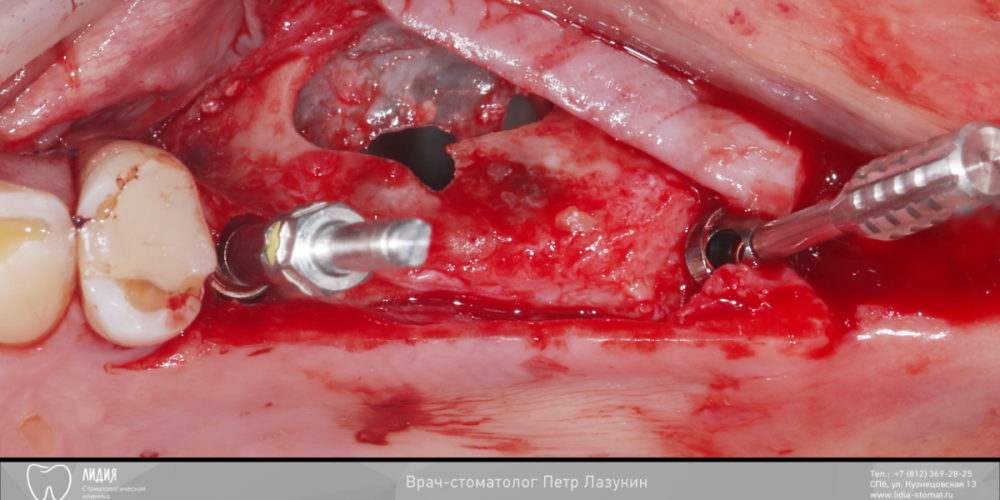

pit Опубликовано 22 декабря, 2021 Поделиться Опубликовано 22 декабря, 2021 Всем привет! Клинический случай. Реферативный пациент. В анамнезе несостоятельная костная пластика и несостоятельный синус-лифтинг (или даже два). Выбрана тактика: имплантация в позиции 25 27 28 (под углом 45 градусов) одномоментно с ОСЛ. В случае очередной неудачи протезирование было бы выполнено протезирование компромиссной конструкцией с опорой на 25 28 импланты. Во время операции произошел полный разрыв слизистой пазухи. Палатинальная стенка была скелетирована и к ней подшита мембрана с формированием купола. Уложен графт ИНТЕРОС, установлены импланты Хай-Тек. Швы. Протезирование МК коронками с винтовой фиксацией с уровня МЮ и платформ через 12 месяцев 13 1 2 Ссылка на комментарий